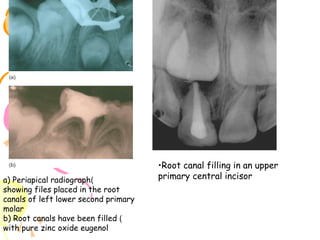

Non-vital pulp therapy⎯primary tooth. (a) A carious, but restorable, non-vital primary molar.

(b) Caries is eliminated and access made to the pulp. Gentle canal debridement is undertaken

with smal files and irrigation. (c) Disinfection of the canal system. A pledget of cotton wool

barely moistened with ledermix is sealed into the pulp chamber for 7-10 days. (d) The tooth

is reopened at a second visit, and after irrigation and drying, a soft mixture of slow-setting

zinc oxideeugenol cement is gently packed into the canals with the cotton-wool

pledget. (e) The pulp chamber is packed with accelerated zinc oxideeugenol cement before

.definitive restoration of the tooth

a) Periapical radiograph)

showing files placed in the root

canals of left lower second primary

molar

b) Root canals have been filled )

with pure zinc oxide eugenol

•Root canal filling in an upper

primary central incisor